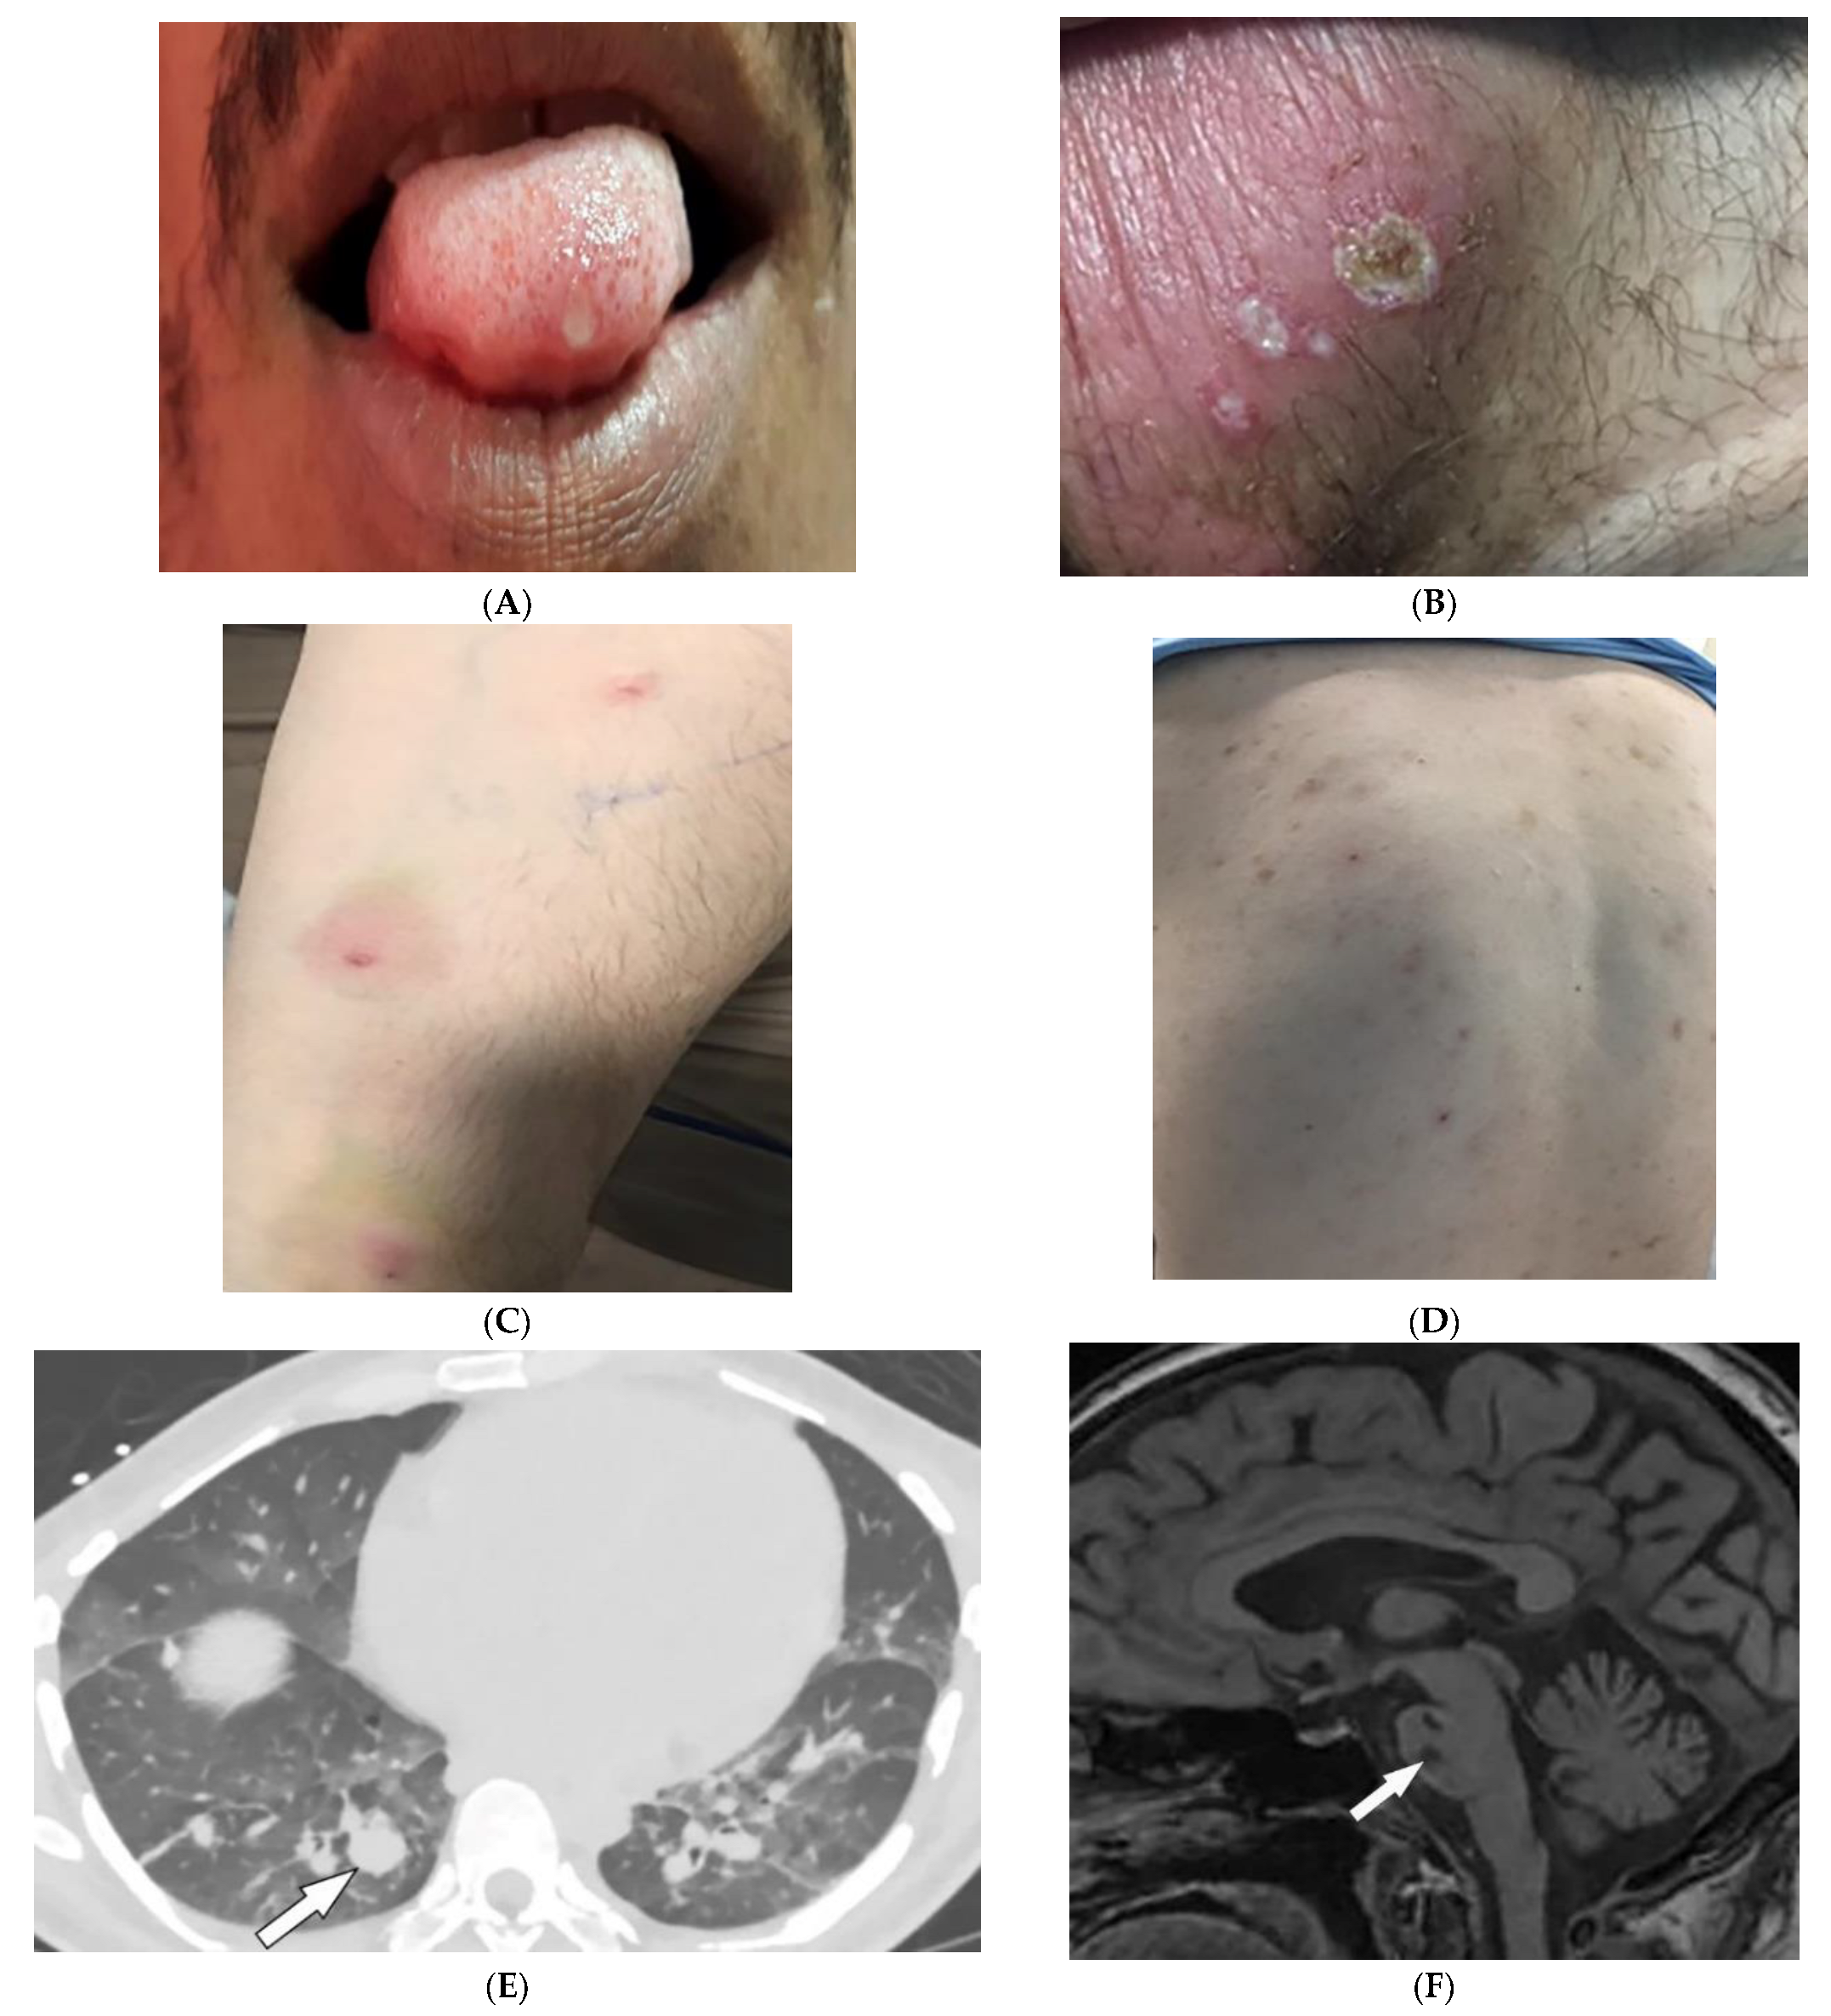

2.7. Behcet’s Disease

| Behcet’s disease | Oral and genital ulcers Ocular findings Vasculitis CNS lesions | Thickening of the aorta and SVC Bilateral pulmonary artery aneurysms Basal ganglia and brainstem lesions |